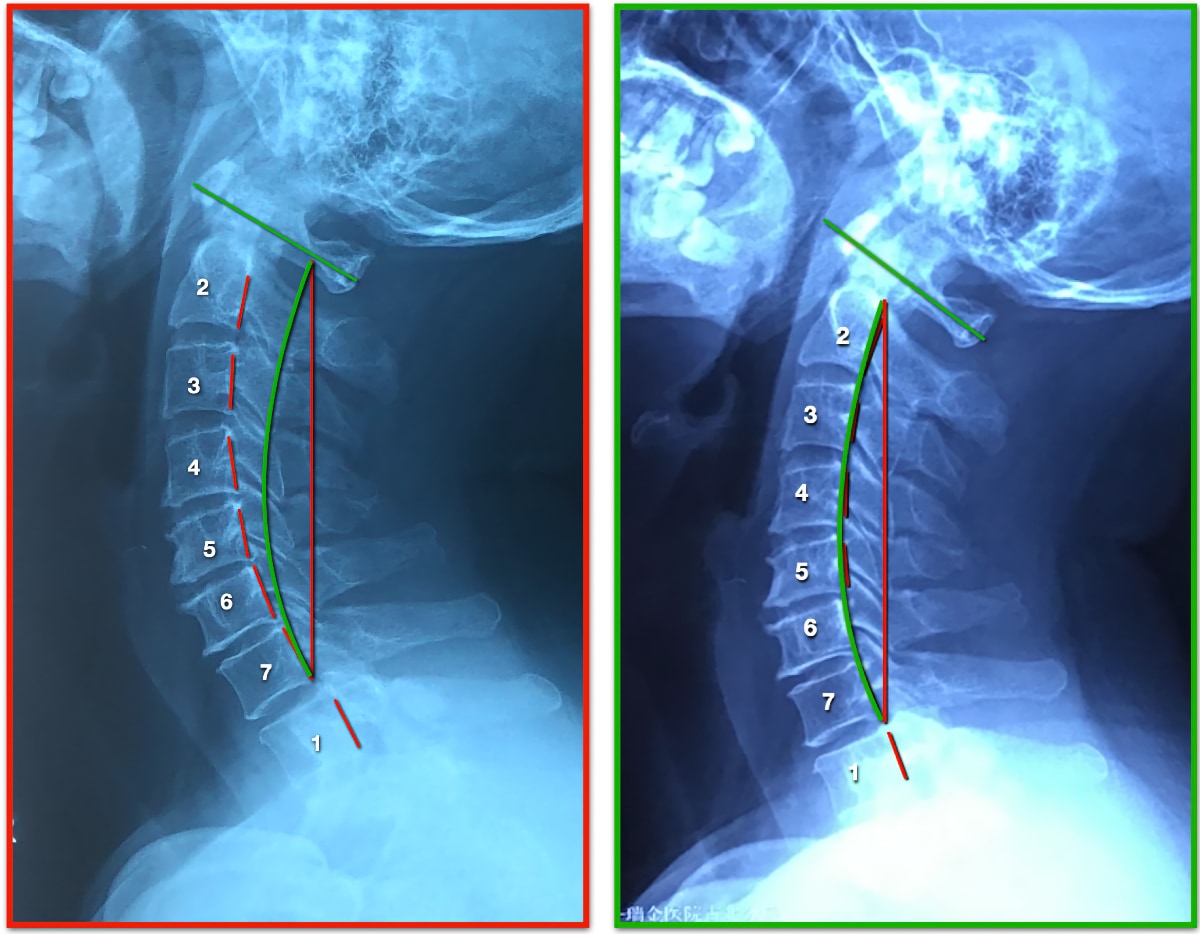

• Forward Head

Continue reading

• Side Neck Curve Case 18Y

• Side Neck Curve Case 52Y